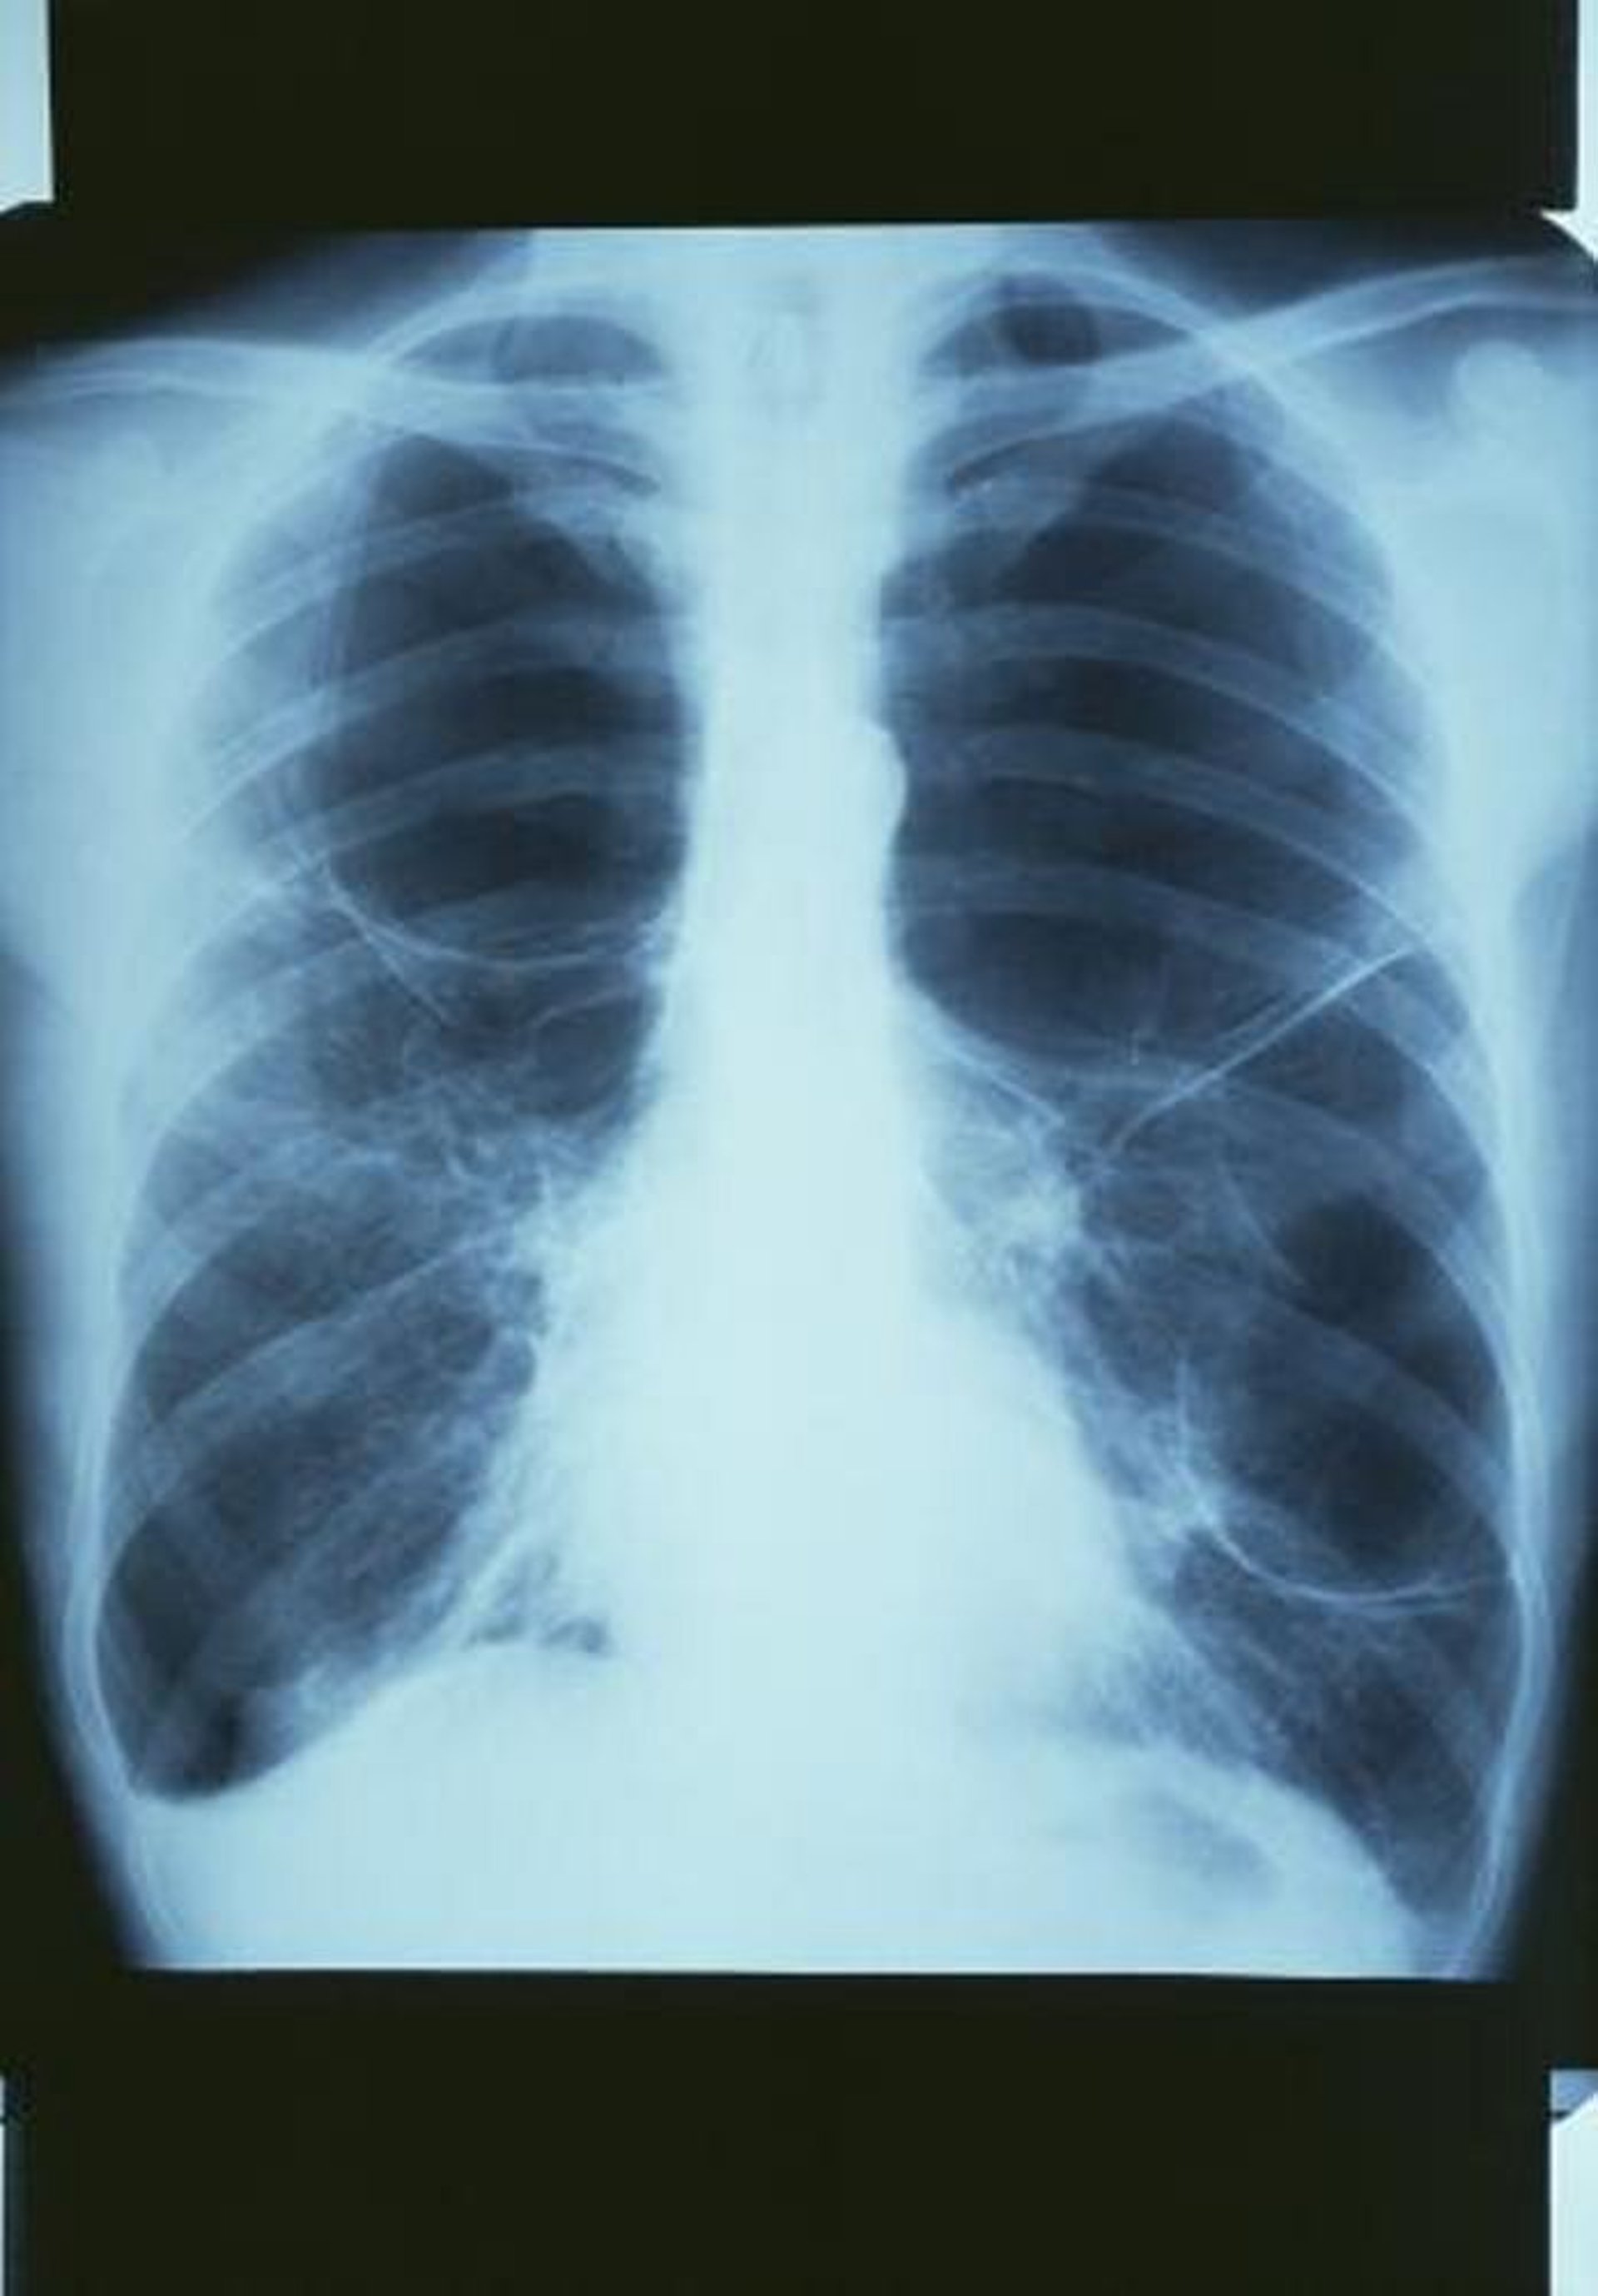

Broncopneumopatia cronica ostruttiva con bolle

Questa radiografia del torace mostra una grande bolla nel polmone in alto a destra e 2 grandi bolle nel polmone sinistro.